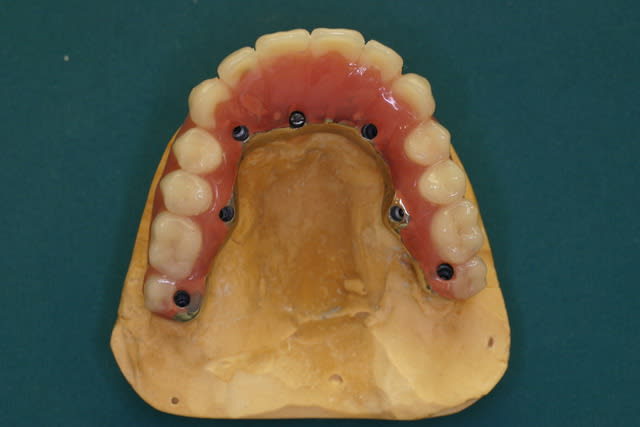

P'tite question, les vis qui tiennent la prothèse en place, sont des vis " plates", simple rainure.

L'axe de certains implants semble un peu trop palatin, mais bon, il n'y a pas de nonos...

1. C est toi qui es malhabile... Rien de plus simple : tu mets ttes tes vis ds la puits, tu les recouvres d homéoplasmine pour les empêcher de tomber hors des puits, tu poses en bouche et tu passes ton tournevis ds homéoplasmine pour visser Très simple et très efficace :-))))

2. Effectivemeznt les plaques zygomatiques ont des émergences palatines mais au définitif j ai ôté les piliers prlongateurs de 3.5 mm et du coup même si sortie palatine plus aucun "débordement" du puits de vissage en dehors de l arcade...

Regarde le provisoire de la MCI : les émergences des plaques au niveau molaires font des bombés hors arcades suite à la pose de piliers monobloc de hauteur 3.5 mm

On pose ces piliers car il faut pouvoir retrouver facilement les têtes d implants 72 h plus tard pour poser la prothèse de transition